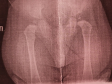

Дисплазия тазобедренного сустава

Больше всего беспокоит: Дисплазия тазобедренных суставов

Здравствуйте, начну с самого начала. Родился малыш с установочной левосторонней кривошеей, в три месяца посетили ортопеда,осмотр был никакой, сказал,что у ребенка все хорошо,он здоров. Но в 9 месяцев мы решили посетить по этой проблеме ещё раз ортопеда другого,где был осмотр даже с узи, тазобедренных суставов,сделали рентген, дисплазия подтвердилась,поставили диагноз: лёгкого остаточное явления кривошеи , разболтанность коленных суставов и дисплазия тазобедренных суставов лёгкой степени, нам сказали пить по три капли аквадетрим, электрофорез,массаж и парафин,и ограничение нагрузки на нижние конечности, но одна проблема,до того как мы обратились ребенок уже начал стоять,знает,что это такое,встал сам. Так вот сам вопрос, можно ли ребенку позволять стоять,если он сам это делает, постоянно,сложно уследить чтобы вообще не стоят,подползает к дивану, в кроватке ц опоры сам встаёт, даже хочет ходить у опоры?если это нельзя,то как можно ему это ограничить,пеленание не подходит, очень активный,нам никакие ортопедические средства сказали не нужны,но как же тогда его ограничивать? спасибо!